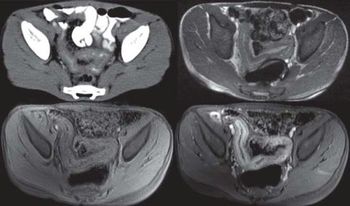

Diffusion-weighted MRI is the most effective MRI technique to detect and evaluate patient response to platinum-based neoadjuvant chemotherapy for late-state ovarian cancer.